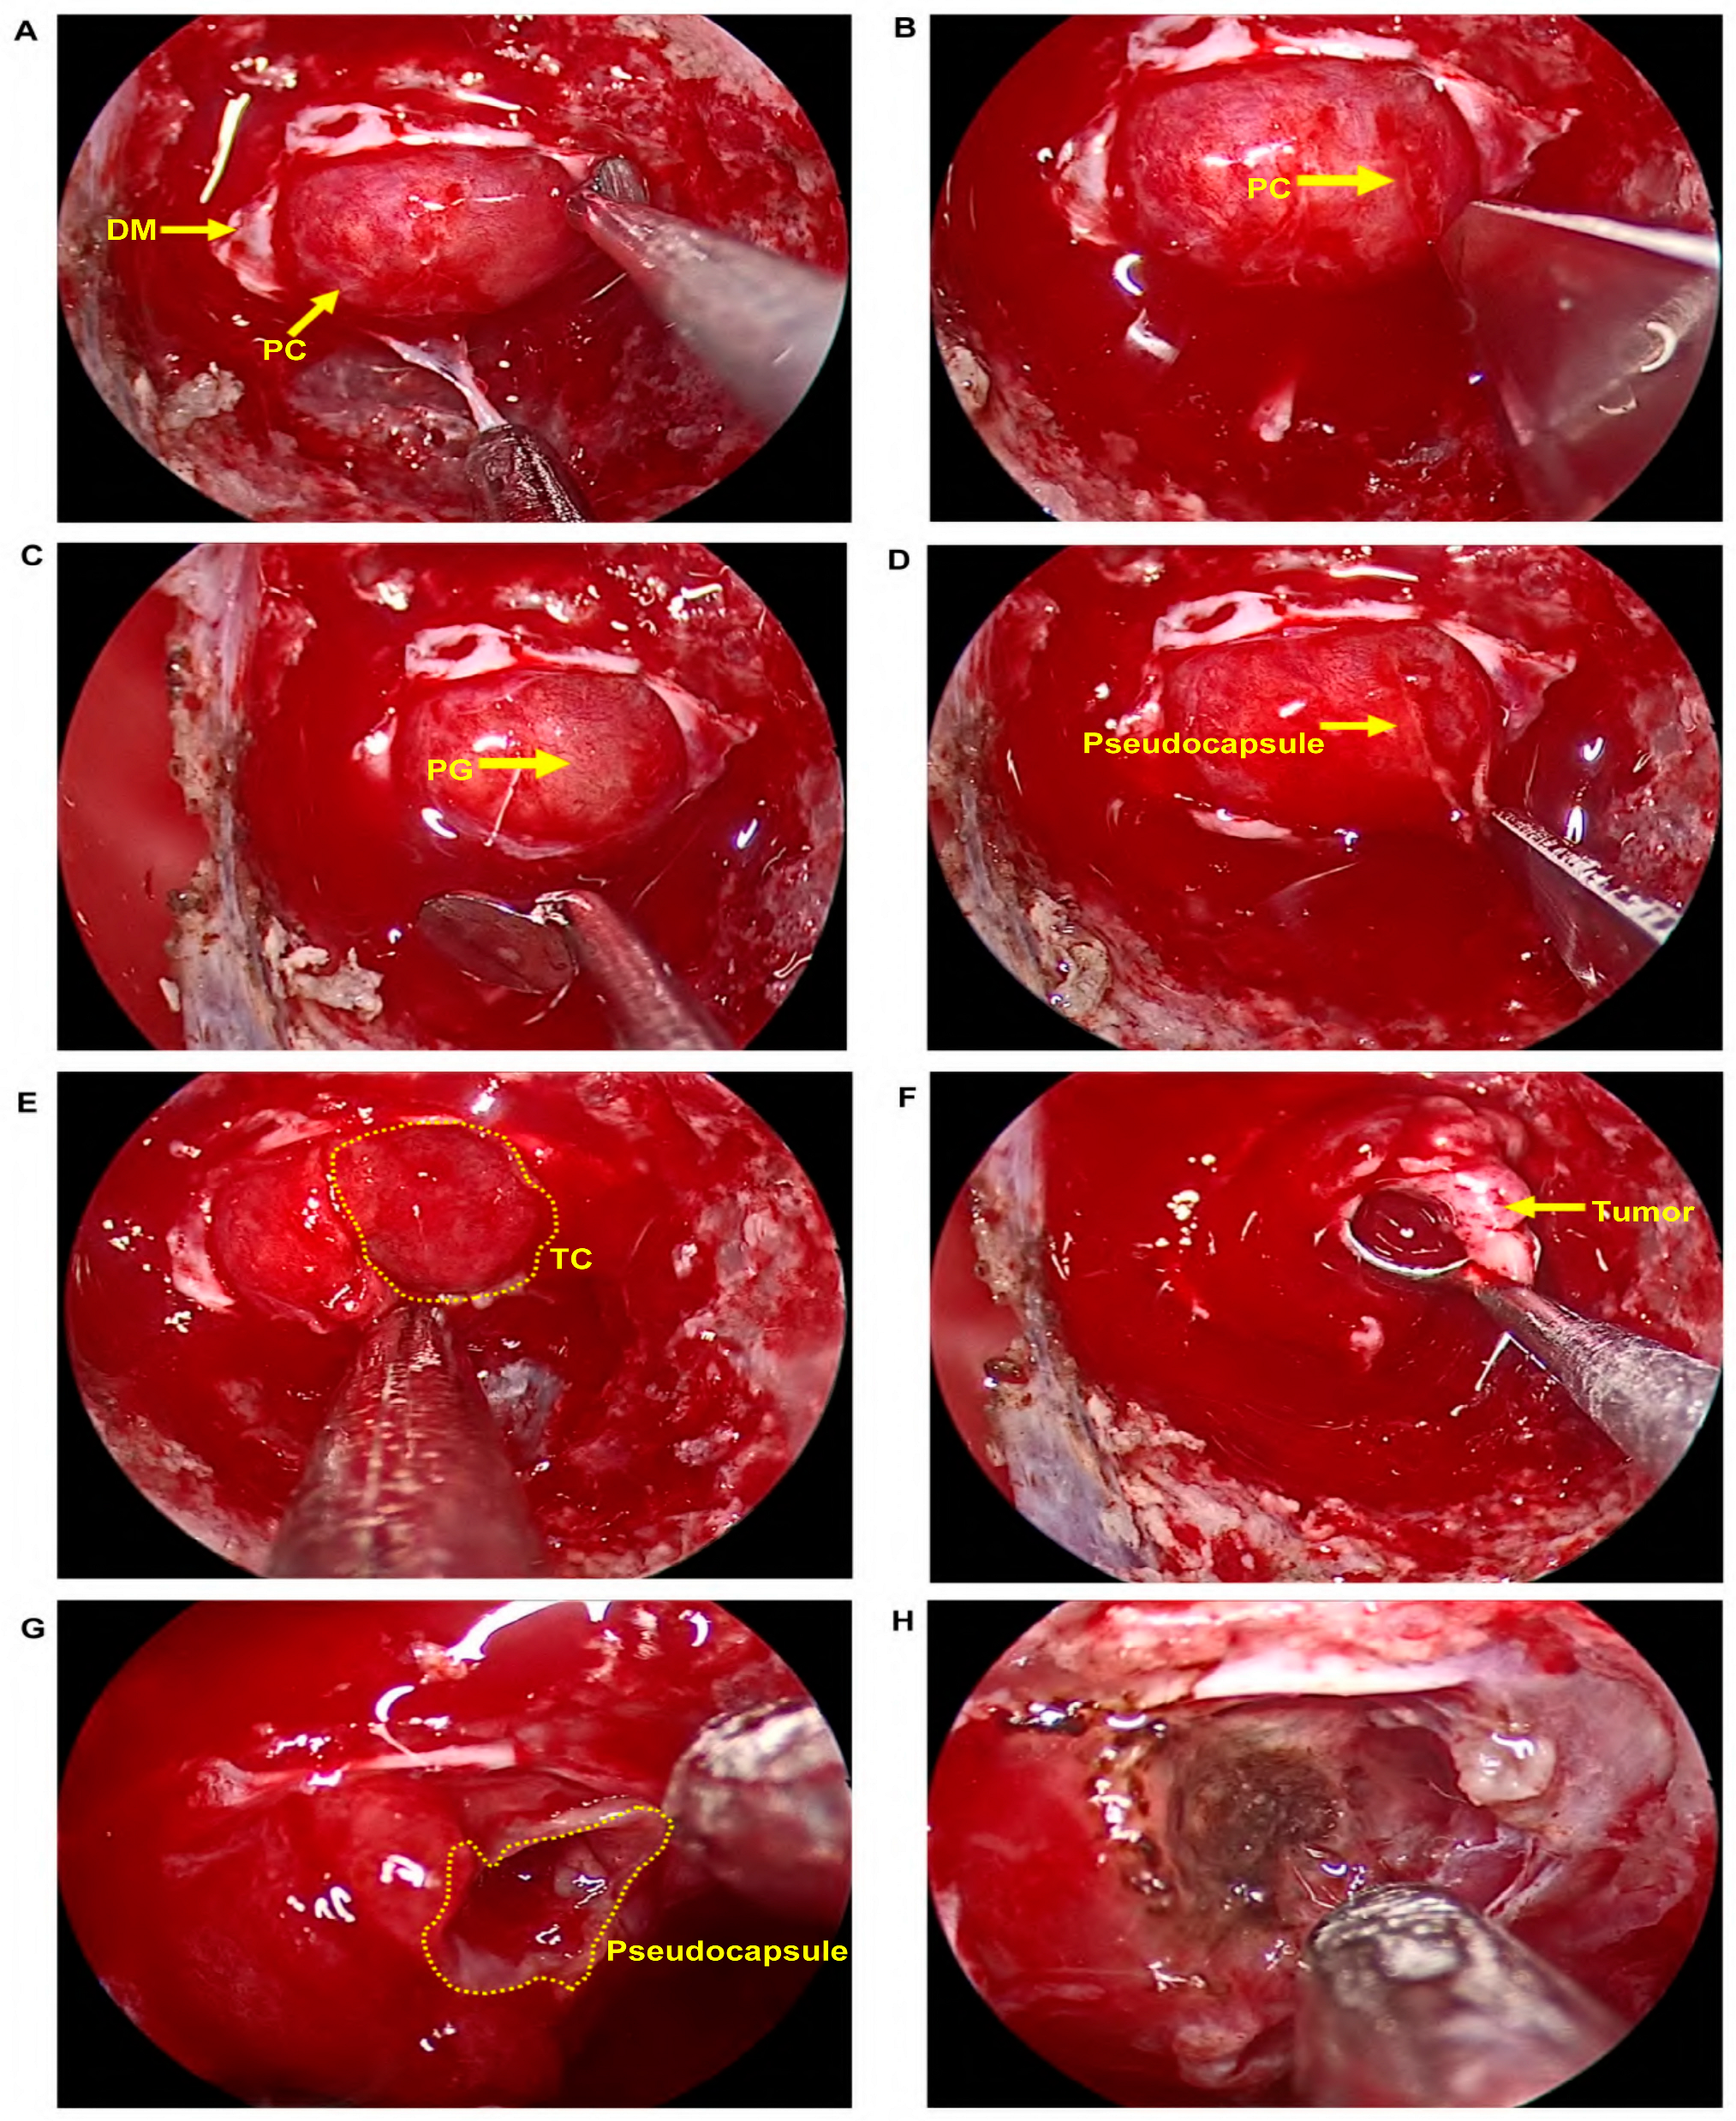

- Nagata, Y.; Takeuchi, K.; Yamamoto, T.; Ishikawa, T.; Kawabata, T.; Shimoyama, Y.; Inoshita, N.; Wakabayashi, T. Peel-off resection of the pituitary gland for functional pituitary adenomas: Pathological significance and impact on pituitary function. Pituitary 2019, 22, 507–513. [Google Scholar] [CrossRef] [PubMed]

- Zhou, Y.; Wei, J.; Feng, F.; Wang, J.; Jia, P.; Yang, S.; Gao, D. Pseudocapsule-Based Resection for Pituitary Adenomas via the Endoscopic Endonasal Approach. Front. Oncol. 2022, 11, 812468. [Google Scholar] [CrossRef] [PubMed]

- Wang, X.B.; Han, T.Y.; Ma, J.G.; He, C.; Xue, L.; Zhang, X.; Wu, Z.B. Pseudocapsule and pseudocapsule-based extracapsular resection in pituitary neuroendocrine tumors. Front. Endocrinol. 2022, 13, 1056327. [Google Scholar] [CrossRef] [PubMed]

- Oldfield, E.H.; Vortmeyer, A.O. Development of a histological pseudocapsule and its use as a surgical capsule in the excision of pituitary tumors. J. Neurosurg. 2006, 104, 7–19. [Google Scholar] [CrossRef]

- Qu, X.; Xu, G.; Qu, Y.; Song, T. The pseudocapsule surrounding a pituitary adenoma and its clinical significance. J. Neuro-Oncol. 2011, 101, 171–178. [Google Scholar] [CrossRef]

- Monteith, S.J.; Starke, R.M.; Jane, J.A., Jr.; Oldfield, E.H. Use of the histological pseudocapsule in surgery for Cushing disease: Rapid postoperative cortisol decline predicting complete tumor resection. J. Neurosurg. 2012, 116, 721–727. [Google Scholar] [CrossRef] [PubMed]